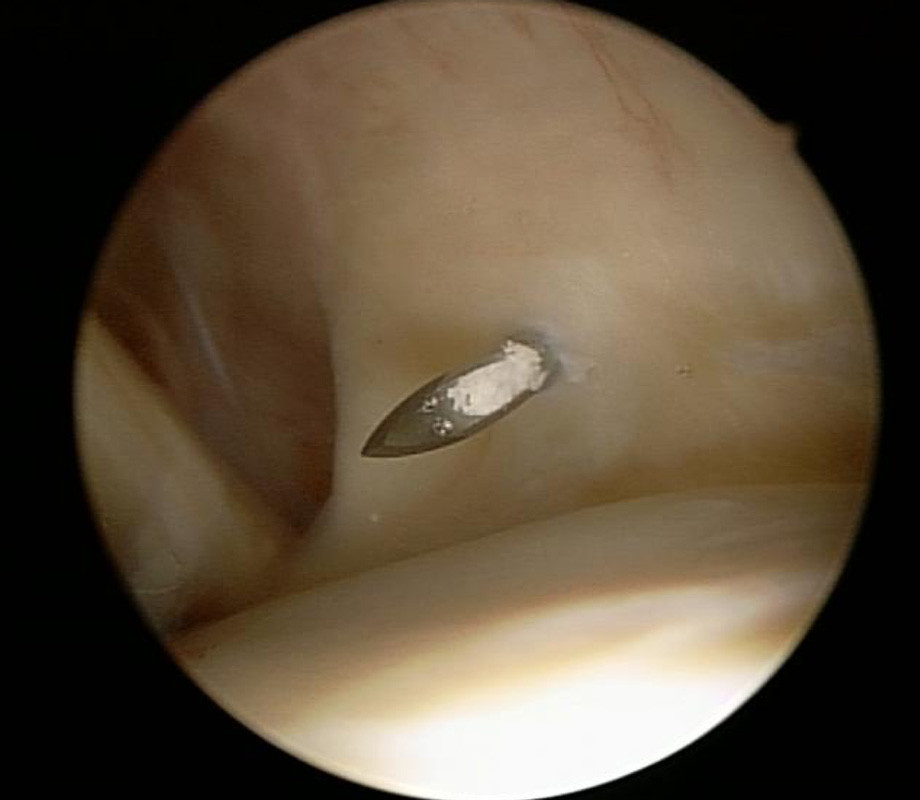

Manchmal liegt der Kalk auch auf der Sehne und führt zu einer starken Entzündung. (Bild 4)